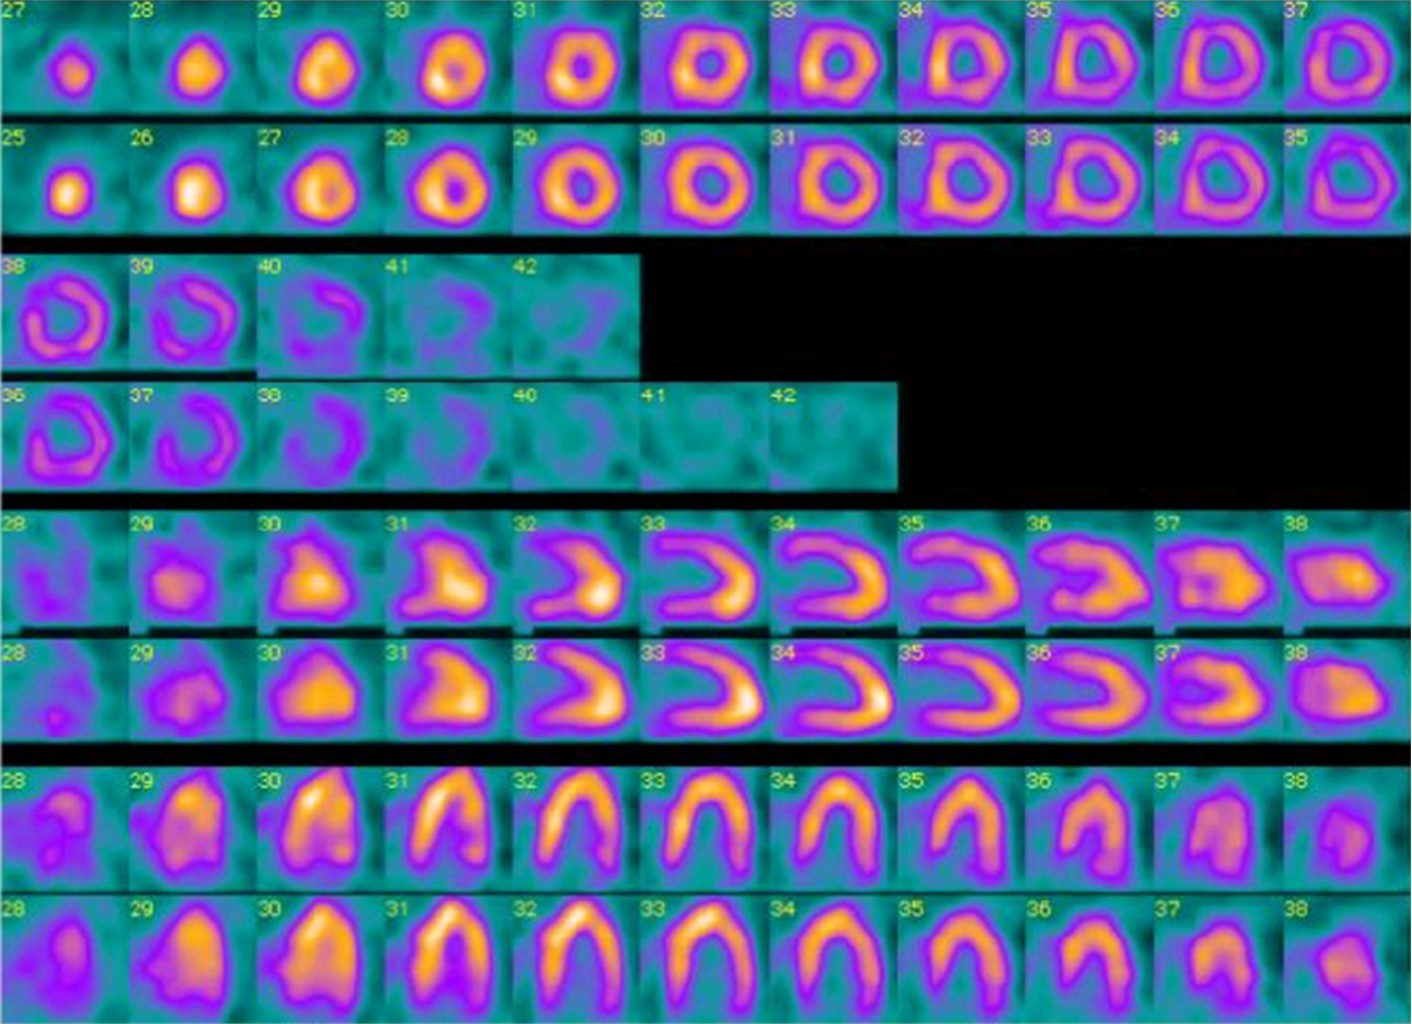

We present a clinical case of a young male in the second decade of life who presented septic shock due to enterobacteria with extended resistance isolated in rectal swab requiring early sepsis campaign guidelines. Had severe pulmonary injury and markers of fibrinolytic activity, pulmonary perfusion is performed by nuclear medicine documenting pulmonary thromboembolism secondary to antithrombin III deficiency and Leiden factor V. It evolves favorably with recovery of ventilatory mechanics tolerating release of mechanical ventilation without compromise of oxygenation or ventilation so it is decided to transfer to internal medicine and hematology.

Figure 2